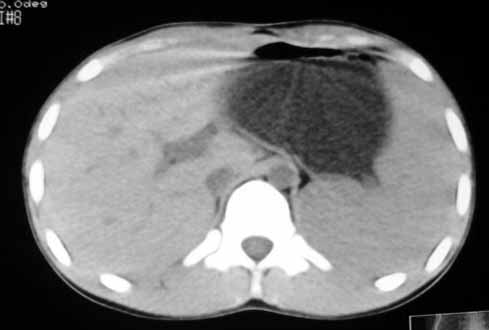

以下是引用zhangzhongshou在2007-5-22 21:04:00的发言:[br]1、脾肿大[br]2、脾脏低密度影,血管瘤?脾梗塞不能除外,建议增强扫描。

以下是引用dyqct在2007-5-22 20:45:00的发言:[br]巨脾,可疑梗塞,建议增强、查血象进一步检查

以下是引用liuyue在2007-5-23 7:57:00的发言:[br]腹主动脉周多个肿大淋巴结,脾大伴三角形低密度影,肠腔积气,考虑:1淋巴瘤2脾大伴梗塞3肠腔积气(肿大淋巴结压迫所致)